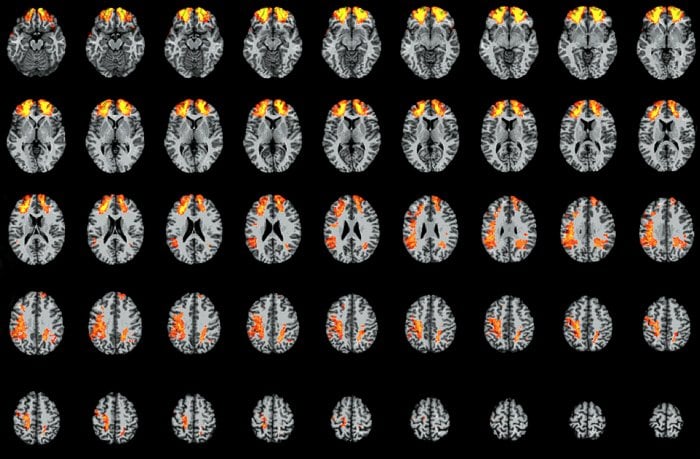

A technique called voxel-based lesion-symptom mapping allowed the team to pool data from the veterans’ CT scans to create a collective, three-dimensional map of the cerebral cortex. They divided this composite brain into units called voxels (the three-dimensional counterparts of two-dimensional pixels). This allowed them to compare the discourse comprehension abilities of patients with damage to a particular voxel or cluster of voxels with those of patients without injuries to those brain regions.

The researchers identified a network of brain areas in the frontal and parietal cortex that are essential to discourse comprehension.

“Rather than engaging brain regions that are classically involved in language processing, our results indicate that discourse comprehension depends on an executive control network that helps integrate incoming language with prior knowledge and experience,” Barbey said. Executive control, also known as executive function, refers to the ability to plan, organize and regulate one’s behavior.cogn